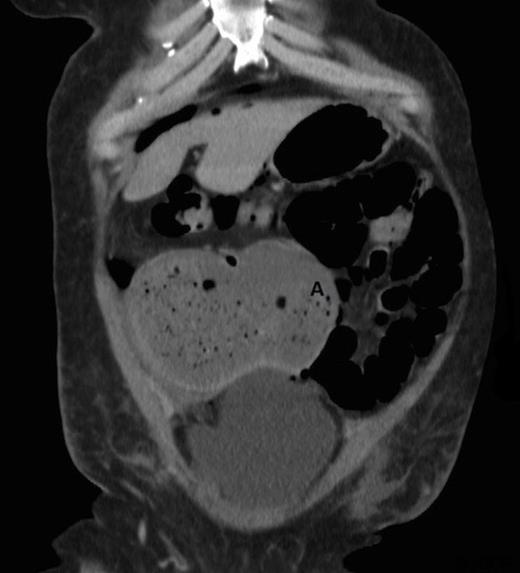

On the first post-operative day, the patient developed a grossly distended abdomen. Paralytic ileus was presumed and the patient was maintained nil by mouth for several hours until she passed flatus. Her abdomen remained distended over the next five days and she continued to complain of intermittent abdominal discomfort. During this time, however, she was tolerating a normal diet and passed loose stools on two occasions. On the fifth post-operative day she complained of a sudden increase in pain and a “popping” sensation in her lower abdomen. Laboratory results after this event, showed a marked inflammatory picture, with a white cell count of 12.5×109/L and C-reactive protein of 203.8mg/L. Abdominal x-ray showed free intraperitoneal gas but no evidence for overt bowel obstruction. A computerised tomography (CT) scan of the abdomen and pelvis with oral and IV contrast showed the caecum lying horizontally with the caecal pole extending towards the left (Figure 1). No air-fluid levels were seen to suggest ileus or mechanical obstruction.

CT scan showing abnormally positioned caecum with caecal pole extending to the left side (A = caecal pole)

Abdominal x-ray is the mainstay of diagnosis. It reveals a dilated and abnormally positioned caecum ranging from transverse to vertical lie.(3,7) Barium enema demonstrates projection of the gas-dilated caecum anterior to the barium filled ascending colon. CT scan often demonstrates an abnormally positioned caecum. Figure 1 shows the caecal pole extending to the left. Only moderate dilatation was present in the CT as perforation had already occurred.